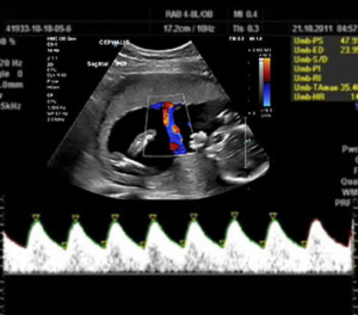

Multivessel color Doppler

This technique measures blood flow in the umbilical cord, fetal heart, and other blood vessels. It is used to evaluate the health of the placenta and assess potential complications such as fetal growth restriction.